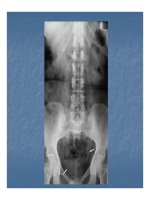

4. Hình cộng đờng bài xuất

Các hình cộng thấy rõ nhất trên chụp UIV.

. Hìnhcộng ở đài thận: nằm ngoài đờng

Hodson.